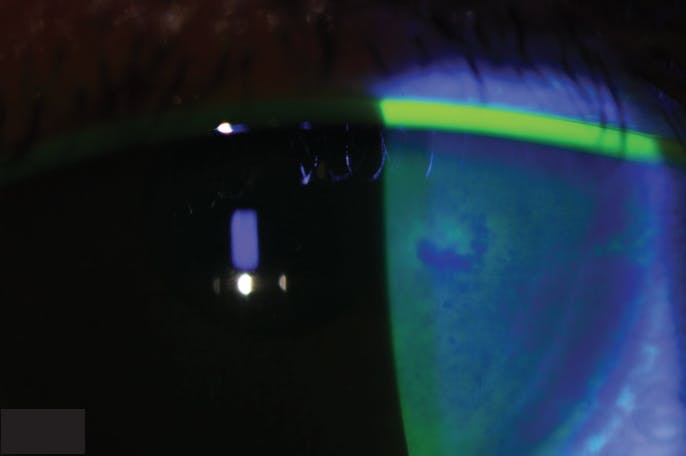

HZO commonly presents as a keratitis. It can arise as an acute keratitis or a chronic-relapsing keratitis that is more difficult to treat. The acute keratitis can yield punctate keratitis or pseudodendrites that stain poorly with fluorescein or rose bengal, which can help differentiate the lesion from a “true” dendrite as seen in HSV keratitis. These pseudodendrites (Figure 3) do not respond to topical antivirals. Nummular keratitis presents as plaques on the stroma in areas of previous epithelial disease and likely represents an immune response.3